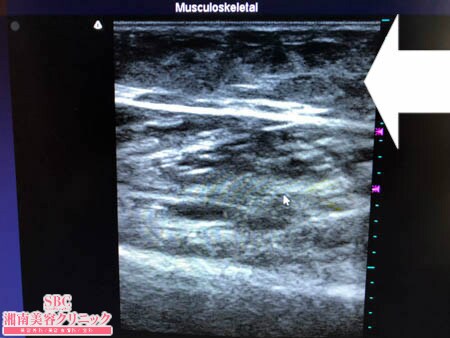

No.205114【脂肪吸引】【動画あり】湘南美容外科脂肪吸引最高責任者である竹田先生による脂肪吸引のフォトギャラリー!むしろなんでいままで脂肪吸引しなかったんだろう!と気が付いた患者様のふくらはぎを細くする!術中3Dタッチビュー・左ふくらはぎ

今回はそんな患者様の

ふくらはぎの脂肪吸引の

術中の模様を紹介しましょう。